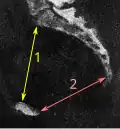

- Conjugata anatomica или diameter recta (анатомическая конъюгата/прямой диаметр верхней апертуры) — между мысом крестца и верхним краем лобкового симфиза — 11,5 (10,8) см

- Diameter transversa (поперечный диаметр верхней апертуры) — наиболее отдалённое между пограничными линиями — 13,5 (12,8) см

- Diameter obliqua (косой диаметр) — между расположенными с противоположных сторон крестцово-подвздошным суставом и подвздошно-лобковым возвышением — 12,0-12,6 (12,0-12,2) см

- Прямой размер таза — между стыком II и III крестцовых позвонков и задней частью середины лобкового симфиза — 12,2 (10,8) см

- Поперечный размер таза — между центрами вертлюжных впадин — 11,5 (10,8)

- Прямой диаметр нижней апертуры — между вершиной копчика и нижним краем лобкового симфиза — 9,5 (7,5)

- Поперечный диаметр нижней апертуры — между седалищными буграми — 10,8 (8,1) см

- Угол наклона таза - угол между горизонтальной плоскостью и плоскостью верхней апертуры таза

- Conjugata vera (истинная гинекологическая конъюгата) — между мысом крестца и самой задней точкой лобкового симфиза — 10,5-11,0 см

- Conjugata diagonalis (диагональная конъюгата) — между мысом крестца и нижним краем лобкового симфиза — 12,5-13,0 см.

Измерение размеров на томограмме низкодозовой компьютерной томографии